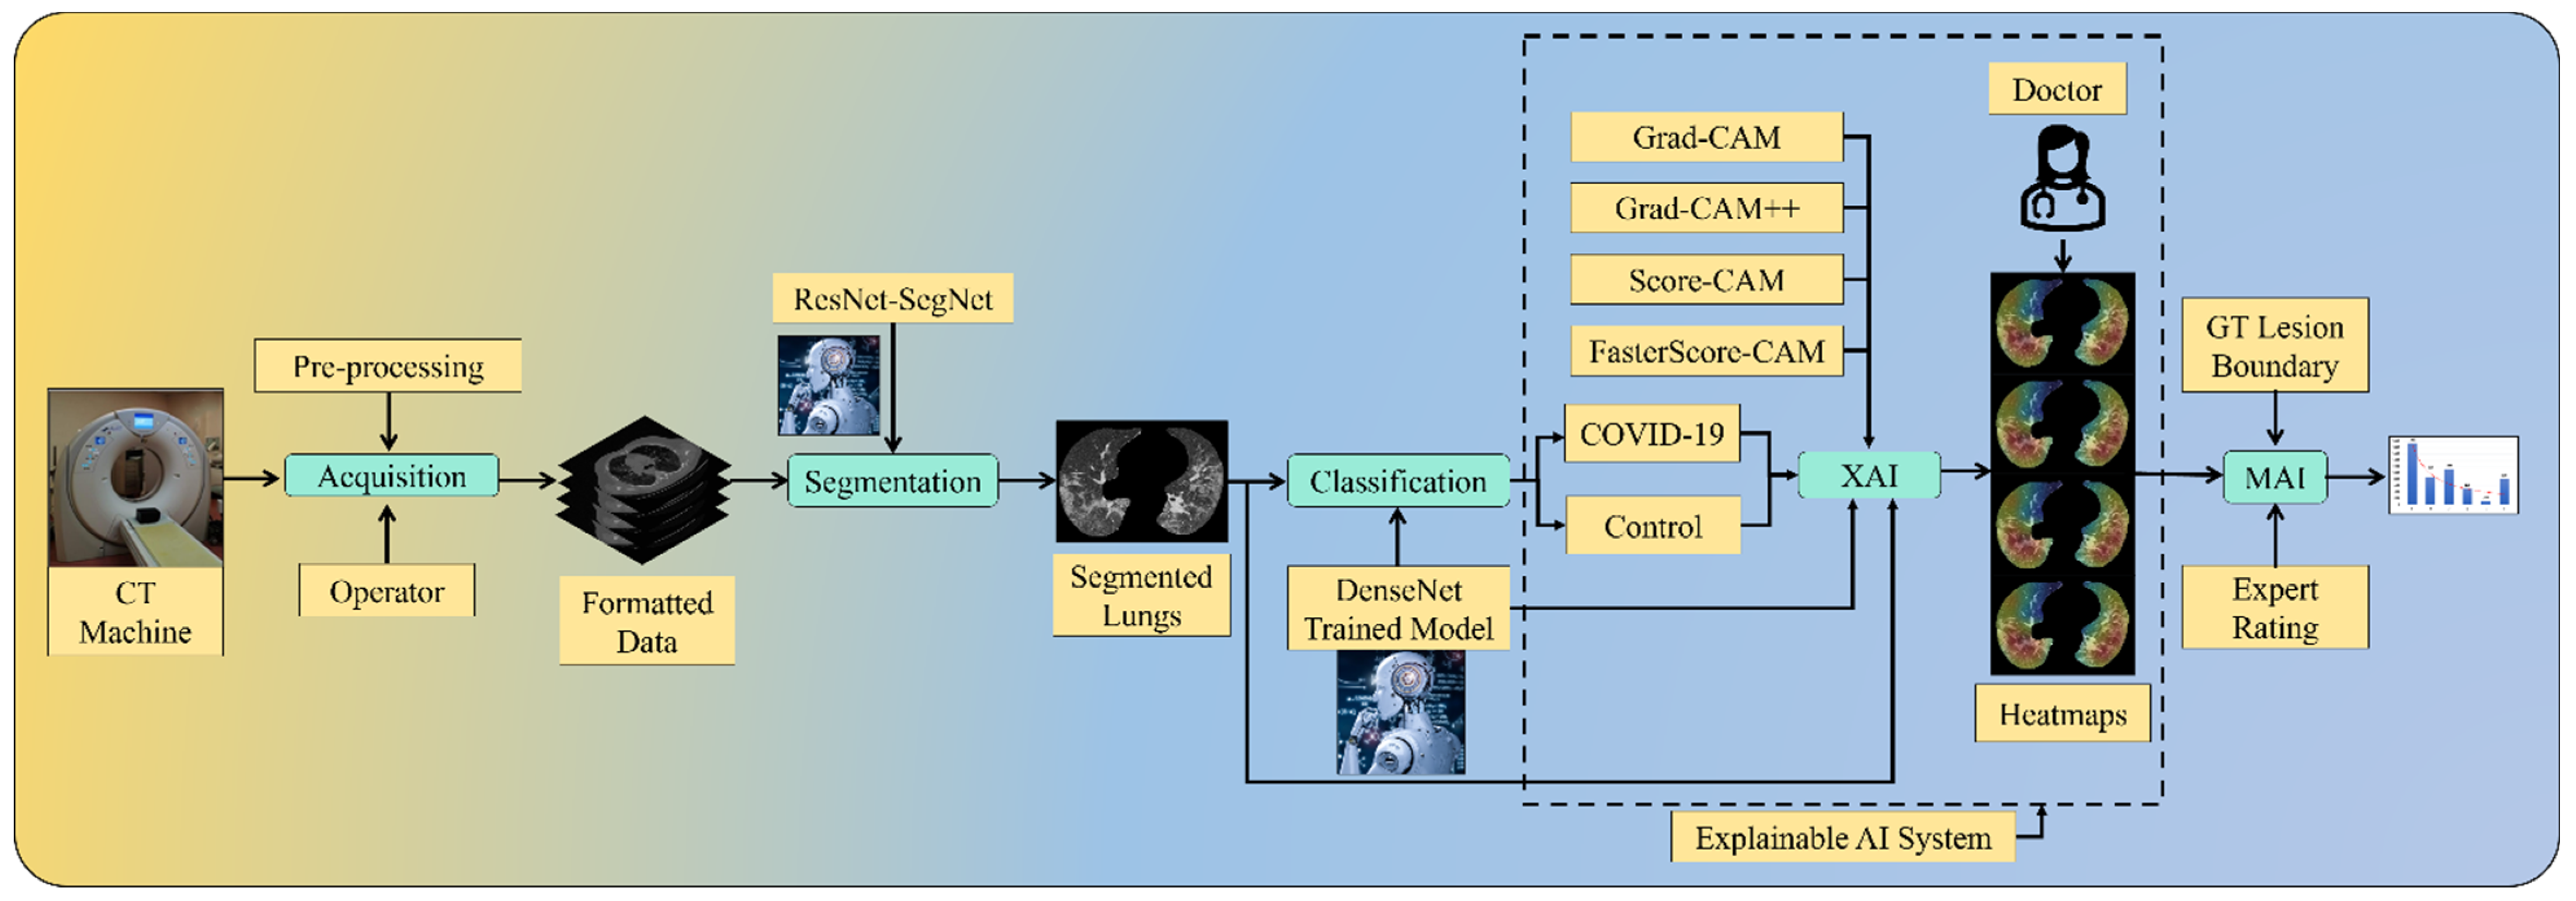

2. Methodology

2.3. Artificial Intelligence Architecture

2.4. Explainable Artificial Intelligence System for COVID-19 Lesion

Four CAM Techniques in Cloud-Based Explainable Artificial Intelligence System